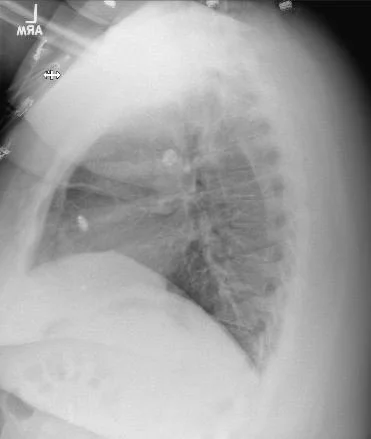

A 24 y.o. woman with a hx of congenital heart disease and complete heart block comes in for dental pain

Hint: the answer is on the cxr

Our patient had a leadless pacemaker which was malfunctioning with spikes on the t waves.

placement by catheter in the RV